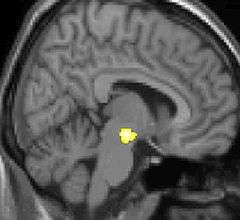

Voxel-based morphometry (VBM) shows brain area structural differences

Some theories suggest that CH attacks may be related to dysfunction of the hypothalamus, this may explain why cluster headaches frequently occur around the same time each day, and during a particular season. One of the functions of the hypothalamus is regulation of the biological clock. Metabolic abnormalities have also been reported. Positron emission tomography (PET) scans indicate the brain areas which are activated during attack only, compared to pain free periods. These pictures show brain areas which are active during pain in yellow/orange color (called "pain matrix"). The area in the center (in all three views) is specifically activated during CH only. The bottom row voxel-based morphometry (VBM) shows structural brain differences between individuals with and without CH; only a portion of the hypothalamus is different.[23]